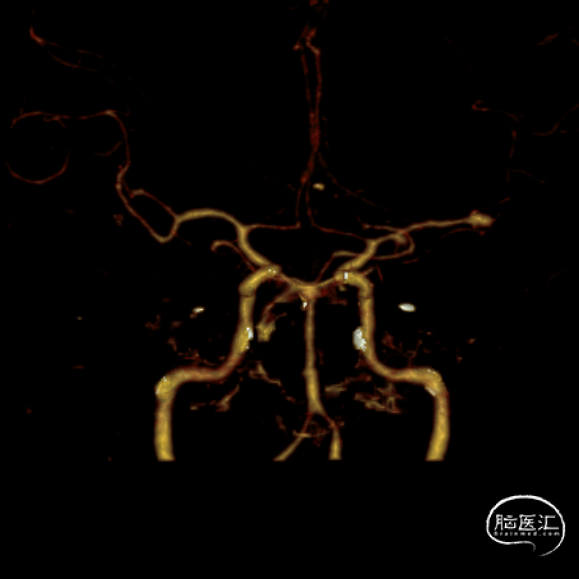

急诊头颅CTA:左侧大脑中动脉M1远端分叉处动脉瘤,左侧大脑中动脉M1段颞干分叉处动脉瘤。

左侧大脑中动脉M1段颞干分叉处动脉瘤

左侧大脑中动脉M1远端分叉处动脉瘤

该例病案,“花开一支,各表一朵”,远端分叉处动脉瘤为责任动脉瘤,但颞干处动脉瘤呈“分叶状”。本次手术最大的难点在于颞干处动脉瘤的处理策略,分期处理的话,在血管痉挛期风险极大提高。如同期处理,从M1水平放支架,对瘤颈没有意义,且两个支架在M1中段可能会有交汇,对豆纹动脉的影响太大。如放在颞干,后期远端动脉瘤万一复发,那补救手术的难度太高。另颞干处为小型动脉瘤,分叶状,如超选两根微导管分区填塞,则空间不够。以上多方面考虑,本例动脉瘤对术者手感考虑比较大,最后颞干处动脉瘤弹簧圈裸栓成功,且经济成本明显下降。

另有报道,动脉瘤尾端在M1段打开可能会波及豆纹动脉,故尽量选用水平段释放支架,对穿支血管尽量减少影响。